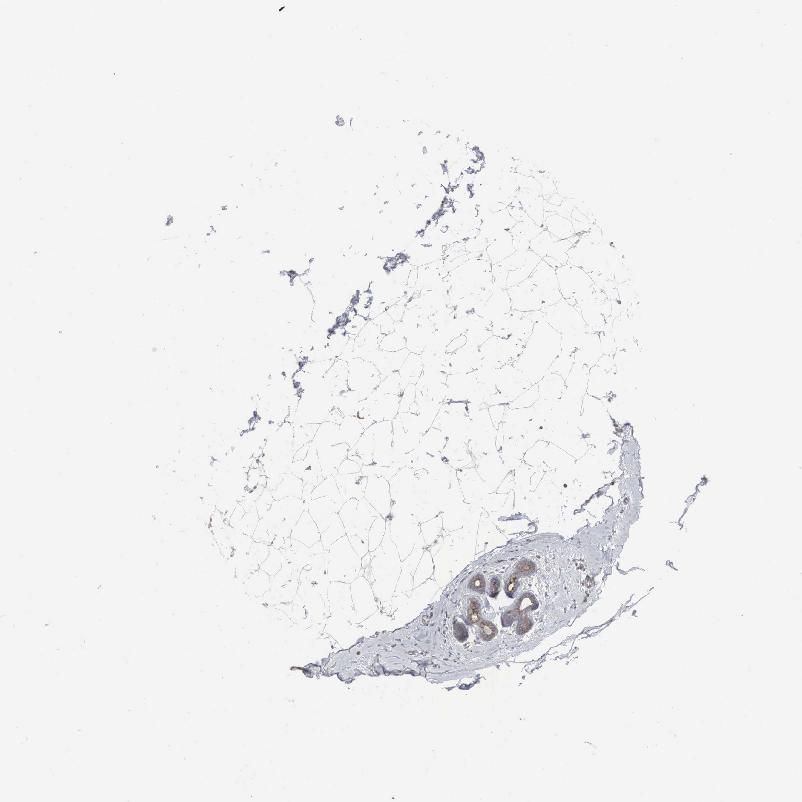

SOFT TISSUE 1 - Antibody stainingi

Antibody staining in the annotated cell types in the current human tissue is reported as not detected, low, medium, or high, based on conventional immunohistochemistry profiling in selected tissues. This score is based on the combination of the staining intensity and fraction of stained cells.

Each image is clickable and will lead to virtual microscopy that enables deeper exploration of all samples and also displays staining intensity scores, fraction scores and subcellular localization as well as patient and tissue information for each sample.

Antibody HPA000387Antibody HPA000922Antibody CAB016204

Chondrocytes -Not detectedNot detected

Fibroblasts Not detectedNot detectedNot detected

Peripheral nerve -Not detectedNot detected

SOFT TISSUE 2 - Antibody stainingi

Peripheral nerve LowNot detected-